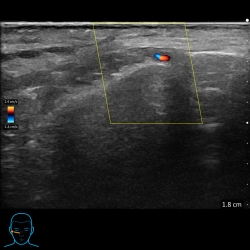

Ultrasound use prior to injecting fillers in aesthetics

02/09/21Since March 2021 I have been using my aesthetic ultrasound scan to improve my patient’s safety when injecting fillers. The ultrasound company tells me I was one of the first in the UK to use...